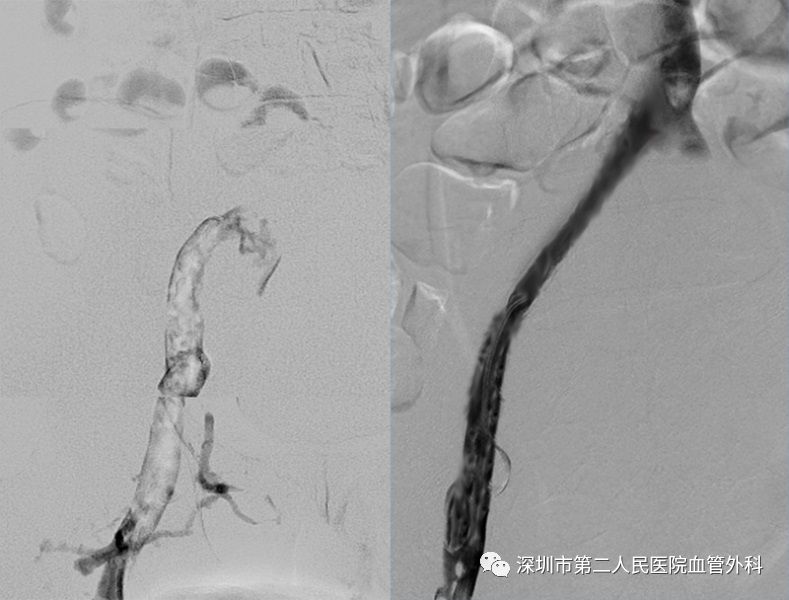

CDT是将带有很多侧孔的溶栓导管,通过静脉穿刺的方法插入血栓中,将溶栓药物通过侧孔持续推注到血栓中,可获得很好的溶栓效果(图10-12)。这种方法对静脉壁损伤轻微,而且能较好地保护静脉瓣的功能。

图11 左:髂静脉内的血栓(白色)。右:置管溶栓后髂静脉恢复通畅

通过适当的手术治疗,肿胀能有效缓解,而且预后较保守治疗好,一般不会出现严重的血栓后综合征。当然,手术后也需要坚持抗凝治疗和弹力袜压力辅助治疗。

图12 微创CDT手术溶栓治疗前(左)、后(右)